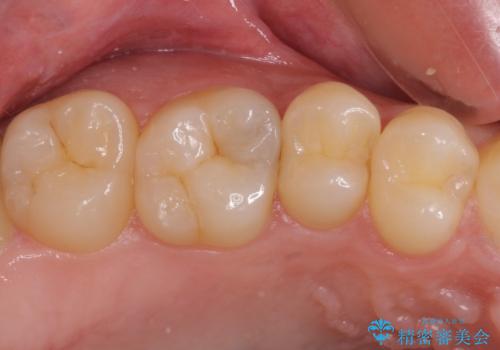

フロスが引っかかる セラミックインレーによるむし歯治療

- ウェブサイトの症例(https://seimitsushinbi.jp/case/9473/)を見て、同じようにフロスが引っかかるとのことで来院された患者様です。

虫歯を除去した後、セラミックインレーにて修復治療を行うこととしました。

セラミックインレー装着後はフロスの引っかかるストレスから解放され、患者様には大変満足していただきました。